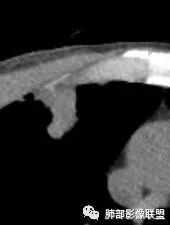

南边:有密度差,外围密度高

南边:宽基底与胸膜相连桃尖征、U型凹陷、刀切征密度均匀,按理这一部分就是典型的炎性病变的特点

这一部分如何分析?

南边:周围晕、细微毛刺都属于炎性特点这一部分单独拿出来类圆形,边缘光滑,按理恶性特征不明显;但是加在一起,转移瘤就不排除总体倾向于炎性,转移瘤不除外